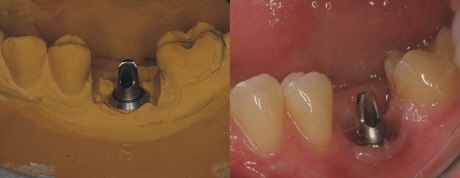

Implantataufbau

Nach der Einheilung des Implantates wird ein individueller Aufbau für das Implantat im Zahnlabor hergestellt. Man sieht den Aufbau links auf dem Gipsmodell des Zahntechnikers und rechts eingeschraubt auf das Implantat.

Auf diesen Aufbau wird die fertige Krone zementiert.